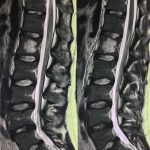

- α

- β

- γ

- δ

- ε

- στ

- ζ

- η

Εικόνα 5 α,β, Μαγνητική τομογραφία (Σεπτέμβριος 2017) μετωπιαίες λήψεις (coronal), γ,δ, εγκάρσιες λήψεις (axial) ,ε,στ,ζ,η οβελιαίες λήψεις (saggital). Παρατηρείται αύξηση των διαστάσεων ,του αιμαγγειώματος σε σύγκριση με εκείνες του 2002.